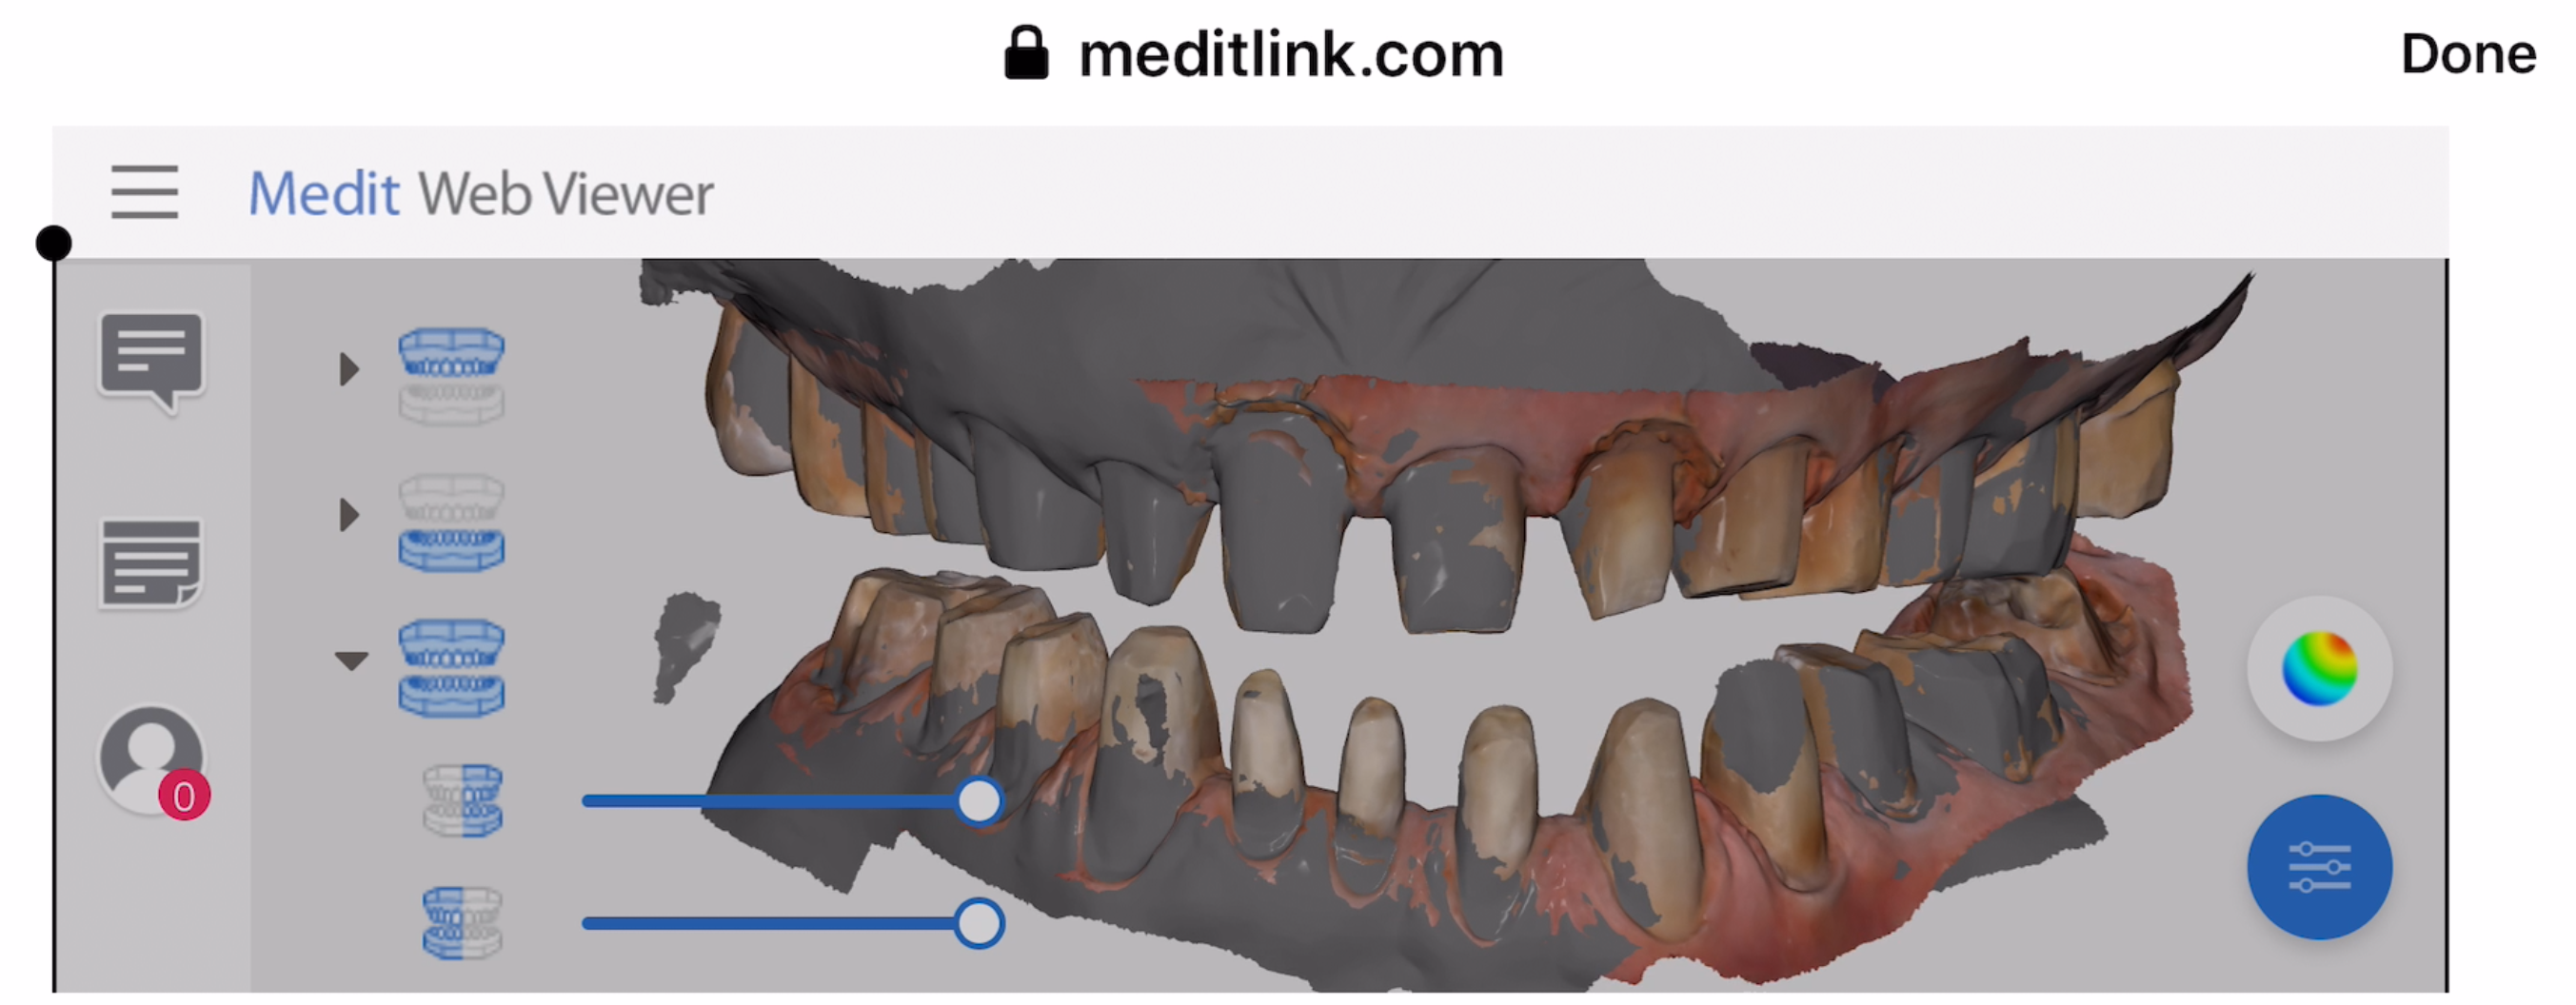

A Medit i500 scan was taken and merged with a CT scan and the distance to bone was measured (5.5 mm’s) giving enough space for soft tissue contouring with […]